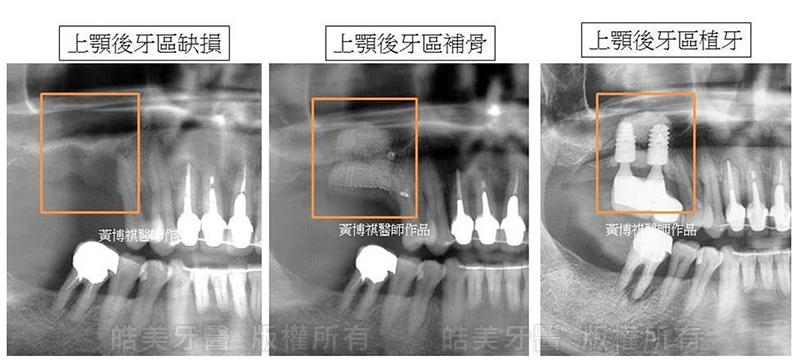

一般的に、上顎臼歯部(上顎の奥歯)には上顎洞という空洞が存在するために、ほとんどの症例において骨量は少なくなっています。上顎の骨は下顎に比べて軟らかいので、歯が抜けると急速に骨吸収をおこし、骨量は減っていきます。インプラント埋入の時には、骨が足りなくなっているのです。

手術方法には、上顎洞底部に骨を造成する「上顎洞挙上術(サイナスリフト、ソケットリフト)」と、骨が少ない場所を避けインプラントを斜めに埋入するがあります。

杜さんは上顎洞の高さが不足しているので、直接インプラントできません。そこで、サイナスリフトで骨を作って、人工歯根を埋め込み、義歯を装着しました。歯の噛み合せ機能は回復しました。

上顎の歯根の欠損が激しく、わずか1mmしか残っていません。サイナスリフトと骨再生誘導法を用いて、厚み12mmまで再建しあとで、インプラントを成功させました。